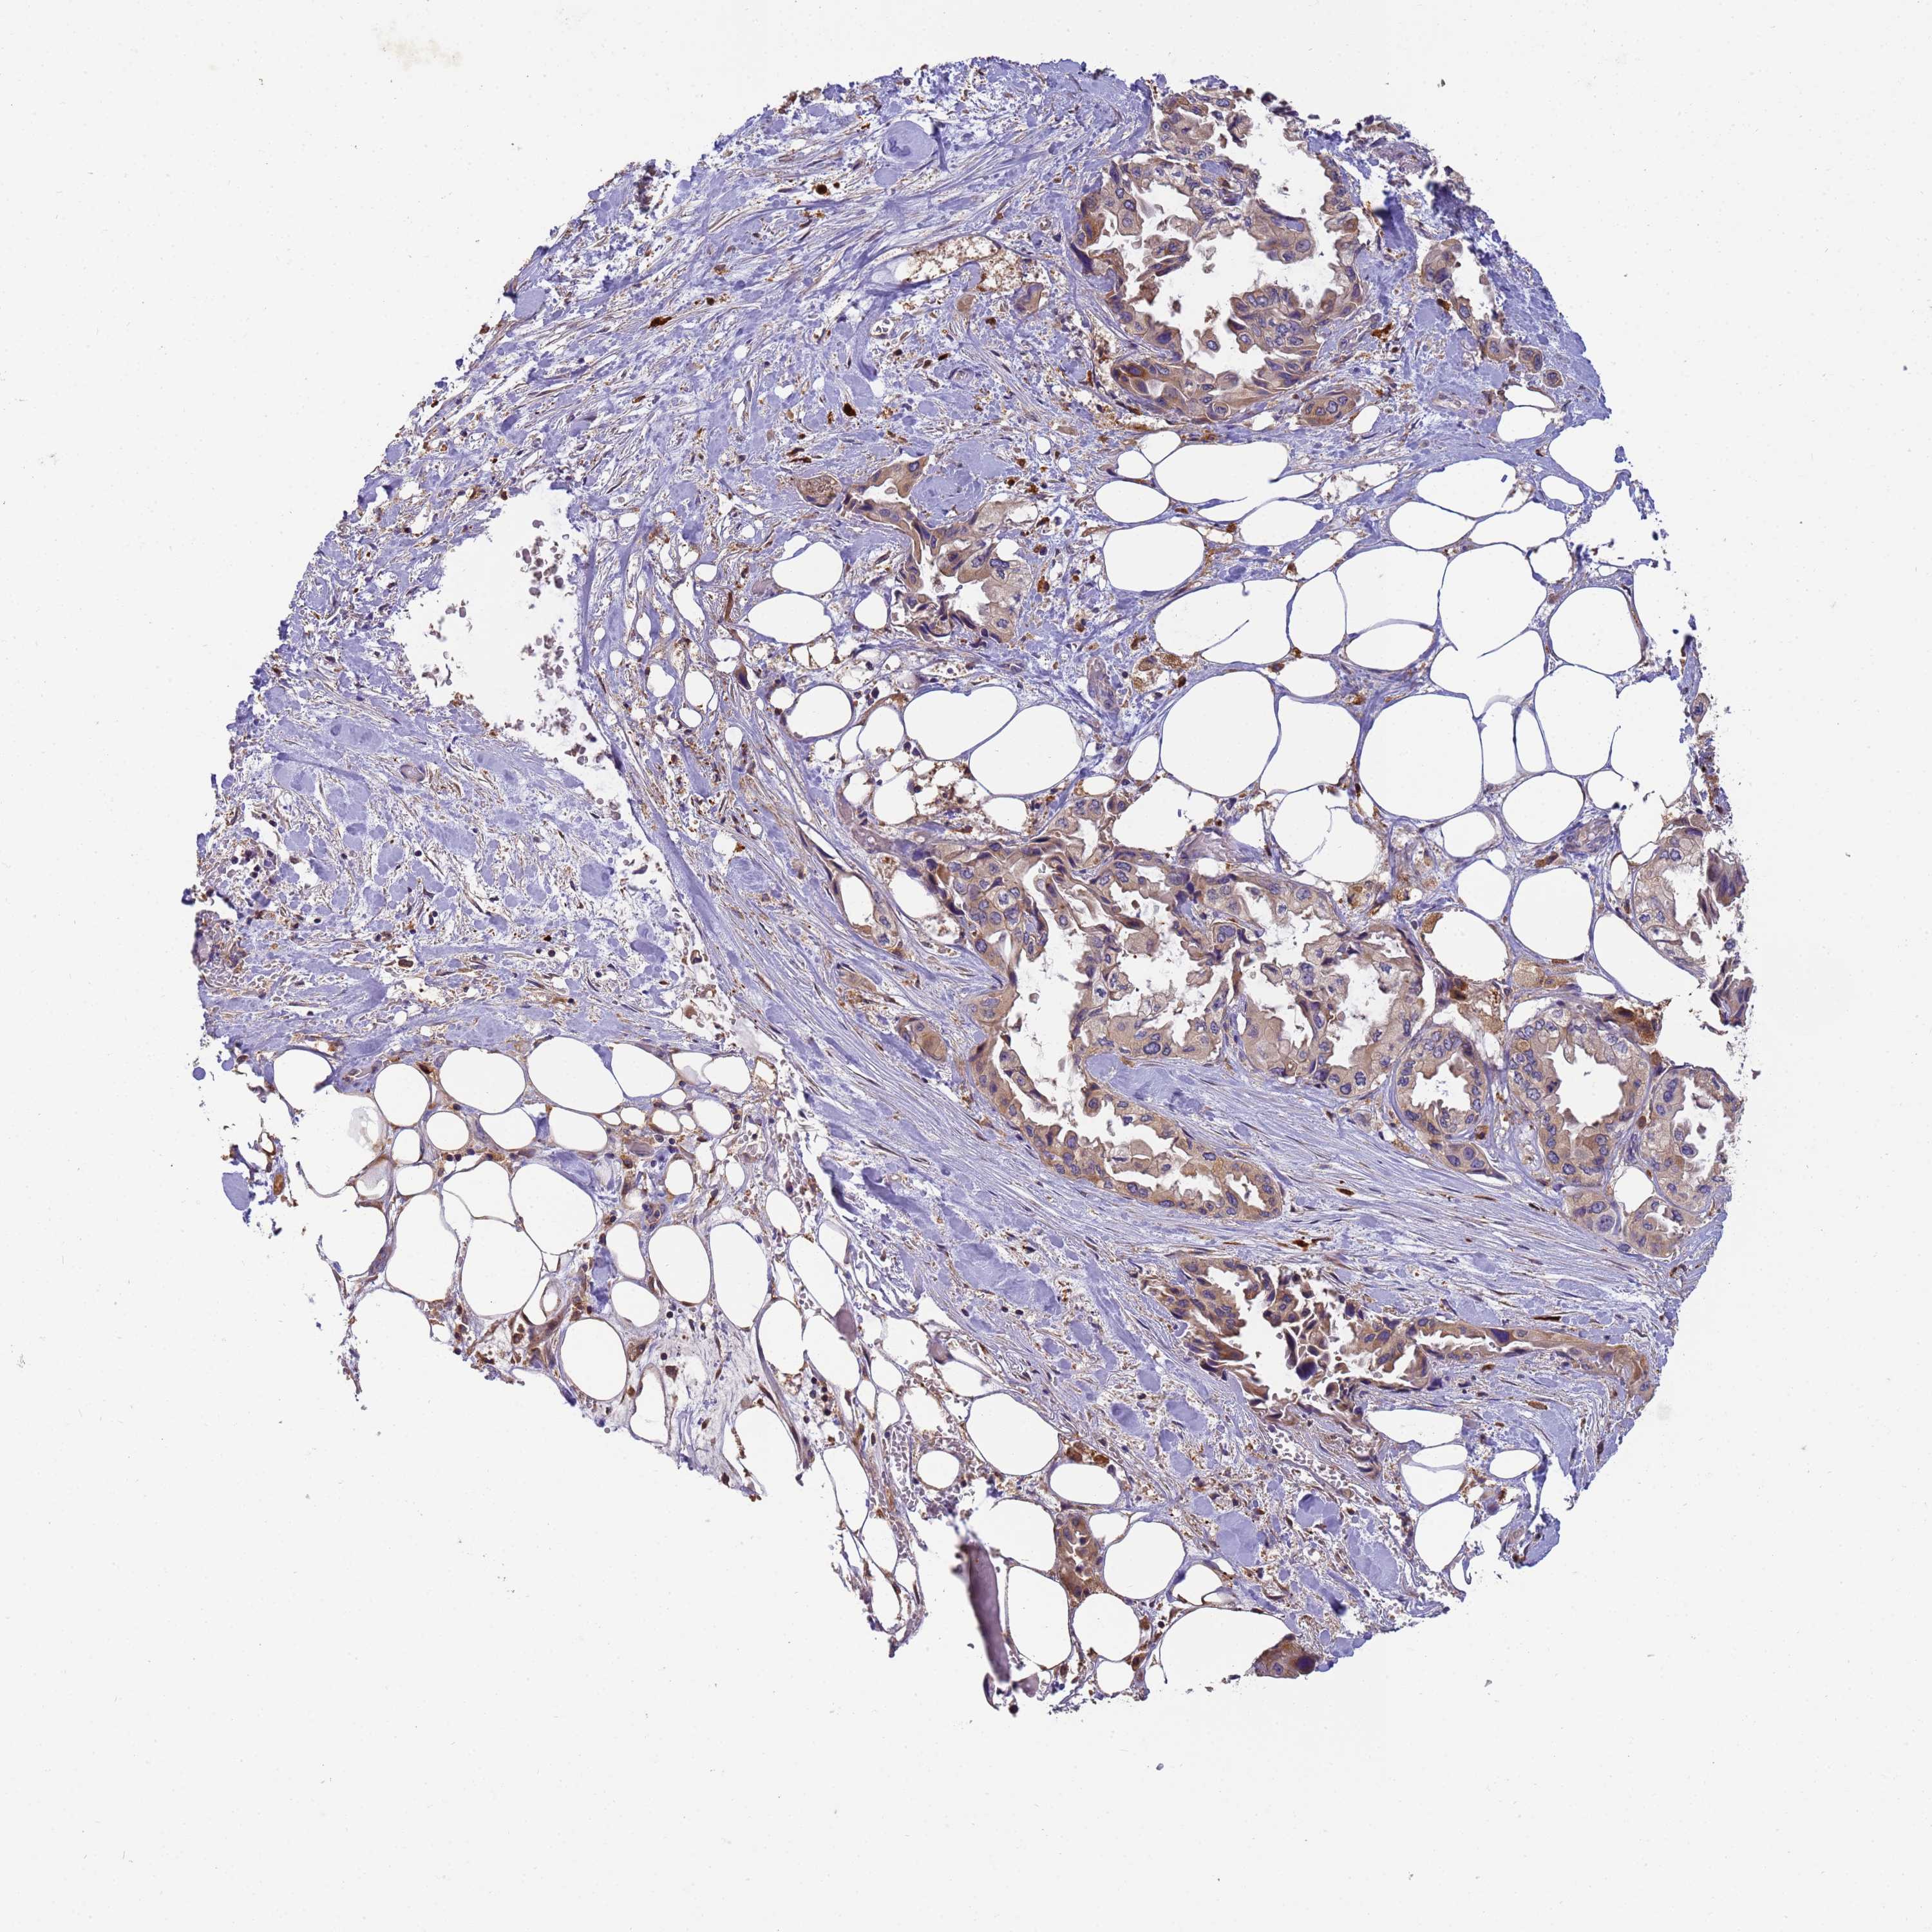

PANCREATIC CANCER - Protein expressioni

A mouse-over function shows sample information and annotation data. Click on an image to view it in a full screen mode. Samples can be filtered based on level of antibody staining by selecting one or several of the following categories: high, medium, low and not detected. The assay and annotation is described here.

Note that samples used for immunohistochemistry by the Human Protein Atlas do not correspond to samples in the TCGA dataset.

Antibody stainingi

Antibody staining in the annotated cell types in the current human tissue is reported as not detected, low, medium, or high, based on conventional immunohistochemistry profiling in selected tissues. This score is based on the combination of the staining intensity and fraction of stained cells.

Each image is clickable and will lead to virtual microscopy that enables deeper exploration of all samples and also displays staining intensity scores, fraction scores and subcellular localization as well as patient and tissue information for each sample.

Antibody HPA040445

Antibody CAB034464

Staining

High

Medium

Low

Not detected

Intensity

Strong

Moderate

Weak

Negative

Quantity

>75%

75%-25%

<25%

None

Location

Nuclear

Cytoplasmic/membranous

Cytoplasmic/membranous,nuclear

Adenocarcinoma, NOS